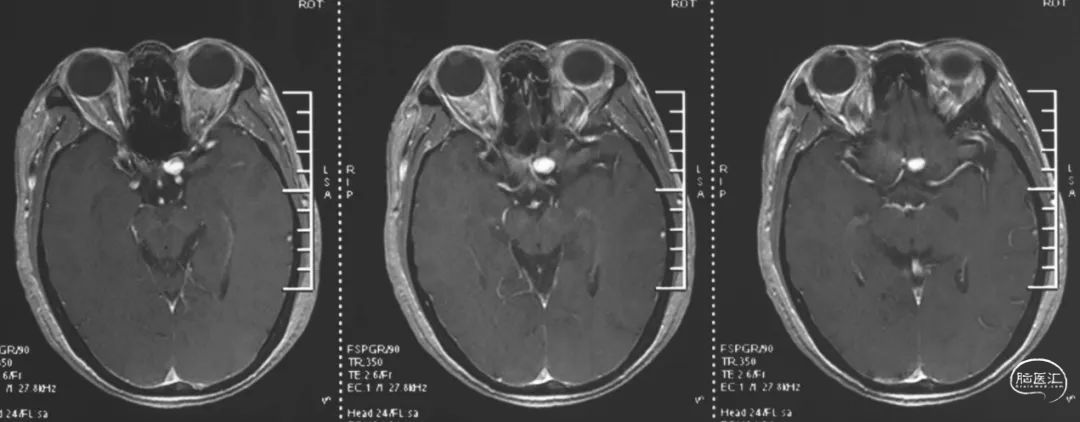

术前MR提示左侧鞍旁血管流空影,增强后瘤壁强化。

术前MRA提示左侧眼动脉段动脉瘤。

造影评估证实左侧眼动脉段动脉瘤,标记测量动脉瘤最大径13mm,动脉瘤颈5.6mm;近端血管直径4.3mm,远端3.8mm,后交通至海绵窦段后部长度24mm。压颈显示前交通开放。